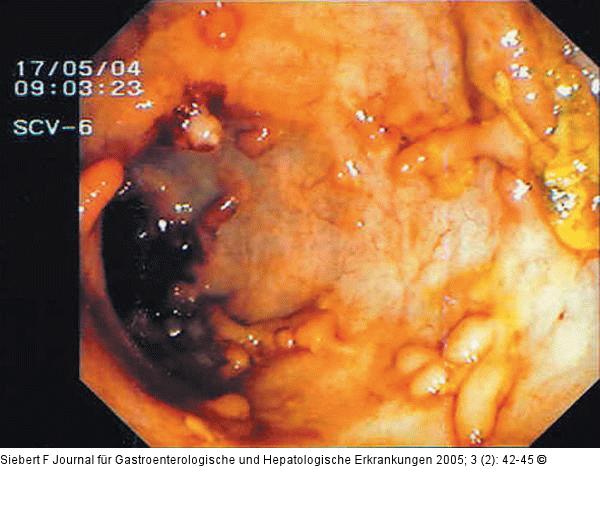

Abbildung 10a-f: Kolon - Reaktionsmuster Aphthen – Ischämisches Ulkus – Ödem, Hyperämie, Ulzeration – Zirkulär-ulzerös narbige Stenose – Pseudopolypös und narbig – Pseudomembranen (von oben nach unten) |

Abbildung 10b